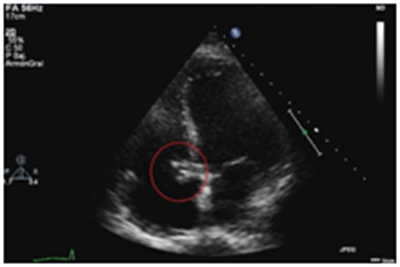

A 79years old man was admitted to the hospital because of dyspnea and fever. Eleven days before admission, the patient had been diagnosed of a Klebsiella Oxytoca urinary tract infection initiating antibiotic treatment with ciprofloxacin. He had history of hypertension, dyslipidemia and multiple urological interventions with internal urethrotomy and dilatation due to urethral stenosis. Clinical examination at admission was normal without signs of heart failure. Electrocardiogram (ECG) showed complete heart block requiring implantation of a temporary pacemaker. Laboratory analysis showed leukocytosis with left deviation and elevated C-reactive protein suggesting an infectious process. In this context, a transthoracic (TTE) (Figure 1) and a transesophageal echocardiography (TEE) was performed showing a large pediculated vegetation on a bicuspid native aortic valve that extends to the left ventricle (LV) and right atrium (RA) (Figure 2). A high velocity jet was observed across the right atrium simulating pulmonary hypertension. Aortic wall was complicated with an aneurysm. Rest of valves and biventricular function were normal.2

Figure 1 Image of a large vegetation in the right atrium in a transthoracic echocardiography view.